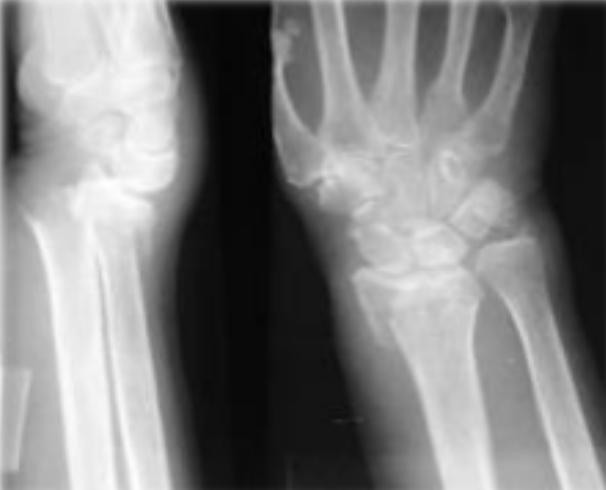

Fractura que se presenta en esta radiografia

Fractura de Smith

Mecanismo de accion de esta fractura

Caida sobre mano en flexion con antebrazo en supinacion

Deformida que presentan los pacientes con esta fractura

En pala de jardin